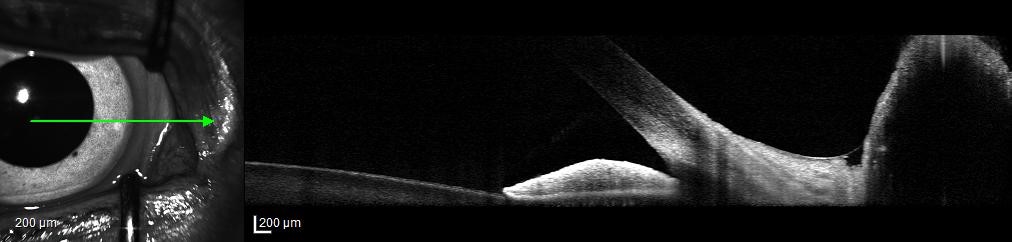

By imaging the iridocorneal angle, changes in the angle can be monitored over the duration of a safety assessment study. Spectral-domain OCT (SD-OCT) provides the capability for noninvasive imaging of anterior segment ocular structures. This technique is particularly suited to topical ocular toxicology studies, but is also applicable to the evaluation of nonocular therapeutics, which have been shown to cause ocular effects. The Heidelberg Spectralis® can obtain images from many of the commonly used laboratory animal species. In addition to anterior segment SD-OCT, posterior segment structures such as the retina and optic nerve can be imaged.

The scanning laser ophthalmoscopy component of the anterior segment OCT provides an image of the cornea, iris and pupil that may also be useful for monitoring changes over the duration of an ocular toxicity study.